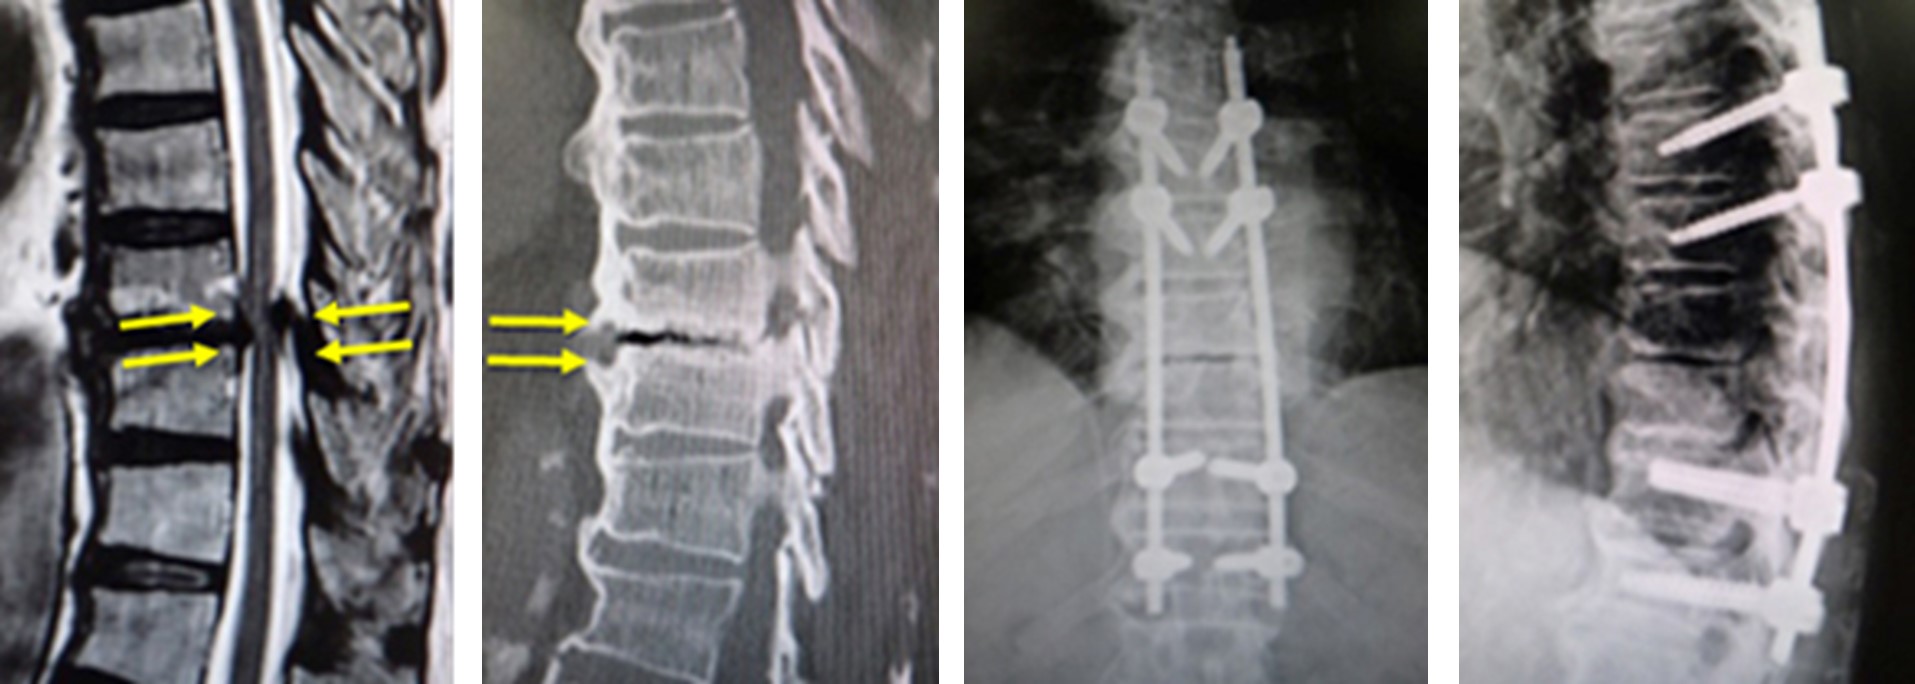

図 上)MRIで造影効果のある脊椎が描出されています。本症例では、がんの既往があり、同部位は転移性脊椎腫瘍と診断されました。椎体が破壊され、腫瘍が脊髄を圧迫しています。

(下)本症例では、従来のように大きな切開を加えること無く、ミスト手術と呼ばれる経皮的椎弓根スクリューを用いた特殊な方法で、小さい皮膚切開で脊椎を安定化しました。がんの患者様に対しては、できるだけ体にかかる負担の少ない低侵襲な方法が望ましいと考えています。